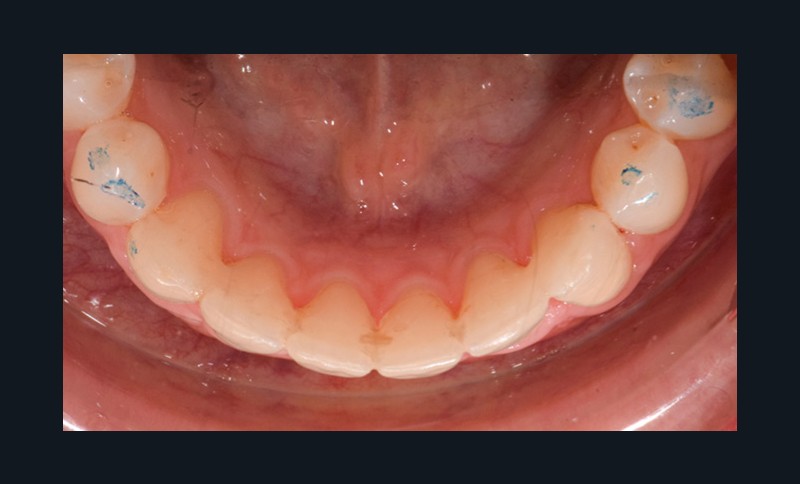

Par exemple, le retraitement d’un patient atteint d’un « Syndrome du fil » [2, 3], au vu de l’état des connaissances imparfaites de l’étiologie de cette situation, méritera une réflexion pour trouver un système de confiance. Une fibre collée est l’une des solutions sécurisantes (fig. 1). Mais, si la langue n’est pas stabilisée au repos comme en fonction, un dispositif amovible type Spring Retainer sera préférable.